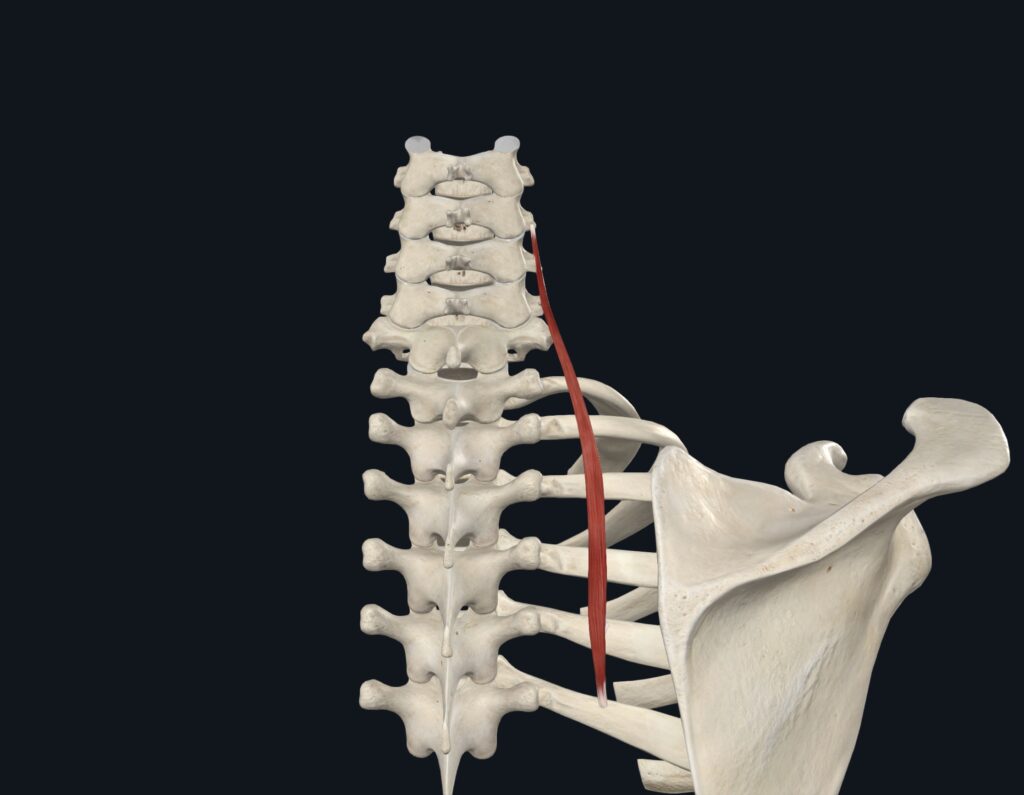

頸長肋筋とは?

頸長肋筋は、頸椎の前方から肋骨にかけて深い場所を走る筋肉です。

頸長肋筋は「寝違え・首の痛み」の隠れた原因筋

頸長肋筋は、首の動きを安定させると同時に、肩甲骨周囲のバランスにも深く関与する重要な筋肉です。

寝違えや肩甲骨内側の痛みが続く場合は、浅層の僧帽筋だけでなく深層の頸長肋筋にもアプローチすることが改善の鍵となります。